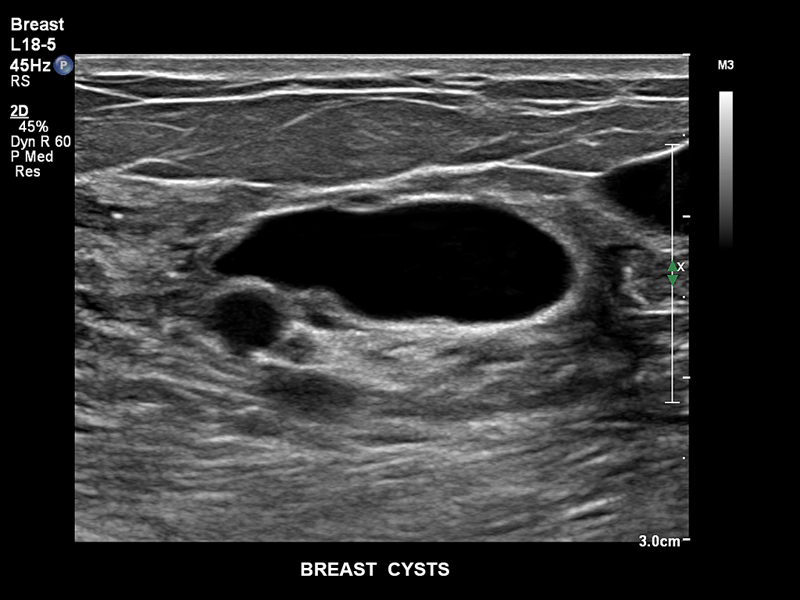

Кисты молочной железы, L18-5